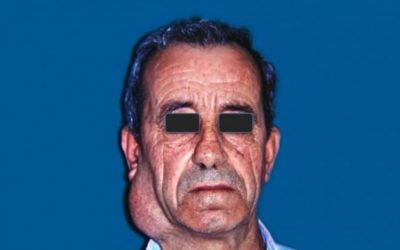

Un porcentaje muy alto de las consultas de Cirugía Maxilofacial, tanto que pueden llegar al 30% de las mismas, se refieren a problemas en la ATM, que es la articulación que une la mandíbula (parte móvil) con el cráneo (parte fija). De ellas, casi todas corresponden a un cuadro que suele tener uno o varios de los siguientes síntomas: dolor en reposo y/o al mover la mandíbula, otalgia (dolor de oído), disminución en la amplitud de los movimientos mandibulares, dolor muscular que puede irradiar al cuello y/o a la parte lateral del cráneo, etc… Casi siempre acompañando a todos o a alguno de esos síntomas, suele asociarse un aumento de la ansiedad y de la tensión emocional, que es la mayoría de las veces quien cierra el circuito desarrollando la explosión de la sintomatología referida. Este complejo de síntomas y signos se denomina Síndrome de disfunción de la ATM.